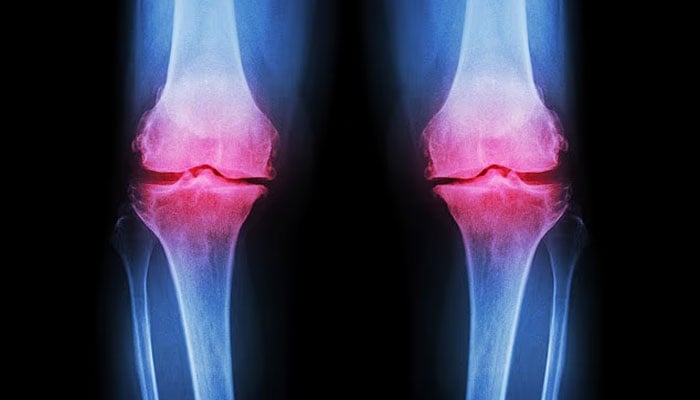

جیسے جیسے دنیا کی آبادی کی عمر میں اضافہ ہو رہا ہے، پٹھوں کی مضبوطی اور ہڈیوں کی کثافت کو برقرار رکھنا ایک بڑا صحت کا چیلنج بن چکا ہے۔ دنیا بھر میں لاکھوں افراد اوسٹیوپوروسس (ہڈیوں کا بھربھرا پن) کے ساتھ زندگی گزار رہے ہیں۔

تاہم اس سے کہیں زیادہ افراد اوسٹیوپونیا سے دوچار ہو سکتے ہیں۔ ایک اندازے کے مطابق 50 سال سے زائد عمر کے تقریباً 40 فیصد افراد کو اوسٹیوپونیا لاحق ہو سکتا ہے، جو ہڈیوں کے بھربھرے یا کمزور ہونے کا ابتدائی مرحلہ ہوتا ہے۔